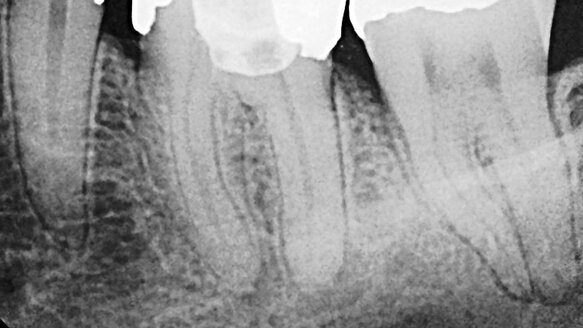

To secure the proper patient, I turned to the referral base of my private practice. A long standing colleague sent me a radiograph and a case history of a patient requiring root canal therapy for tooth # 19 (Figure 1). This was a tooth with an apparently complex root canal anatomy for which a pulpotomy had been done. After meeting with my patient, my assistant and I packed all of the instruments that we would need for the procedure. The two most important pieces of the armamentaria were LightSpeedLSX nickel titanium rotary files (Discus Dental, Culver City, Calif.) and the EndoVac irrigation system (Discus Dental, Culver City, Calif.).

On the day of the live presentation, after anesthetizing my patient, preparing proper access, and creating a glide path, I began instrumentation with LightSpeedLSX. LightSpeed files allow me to create root canal preparations that thoroughly clean the critical apical third without unnecessarily removing root structure coronally. The mesial canals were finished to a size #45 and the distal canal to a size #50. Those sizes might sound large, but because of LightSpeed’s unique, non-tapered design (Figure 2), I know the canals had been properly instrumented, and I had actually removed less overall dentin due to a more conservative coronal preparation.

With instrumentation complete, I began final irrigation with EndoVac. EndoVac irrigation is a ground-breaking, true apical negative-pressure irrigation system. Studies have shown that current irrigation techniques are effective at cleaning root canals coronally, but significantly less effective apically. EndoVac is the only system that can safely deliver full strength sodium hypochlorite to full working length, allowing hydrolysis of tissue and complete canal disinfection. Three unique components of the EndoVac system make this all possible (Figure 3). During irrigation, 17 percent EDTA is also used to remove the smear layer, creating clean canal walls, ready for obturation. After obturating using warm vertical compaction of gutta-percha, the case was complete (Figure 4).